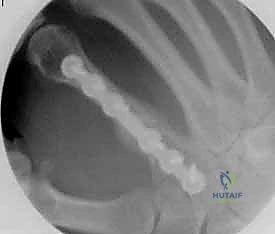

1. التثبيت باستخدام الأسلاك الدقيقة (K-wires)

تُعد هذه الطريقة (Percutaneous Pinning) من التقنيات طفيفة التوغل. يتم إدخال أسلاك معدنية رفيعة جداً عبر الجلد لتثبيت العظم المكسور تحت توجيه الأشعة السينية المستمرة (C-arm) داخل غرفة العمليات.

* الميزة: جروح صغيرة جداً، تعافٍ أسرع للأنسجة الرخوة.

* الإزالة: غالباً ما يتم إزالتها في العيادة بعد 4-6 أسابيع بدون الحاجة لتخدير كامل.

خطوات التثبيت الجراحي - توثيق بصري (Intraoperative Imaging)

يحرص الدكتور هطيف على توثيق خطوات العمل الجراحي لضمان أعلى مستويات الدقة. نستعرض هنا مجموعة من الصور من داخل غرفة العمليات توضح مدى تعقيد ودقة هذه الجراحات:

تتطلب الجراحة انتباهاً خاصاً للأوتار الباسطة والقابضة والأعصاب الدقيقة المحيطة بالعظام. استخدام تقنيات الجراحة الميكروسكوبية (Microsurgery) يضمن عدم الإضرار بهذه الأنسجة الحساسة.